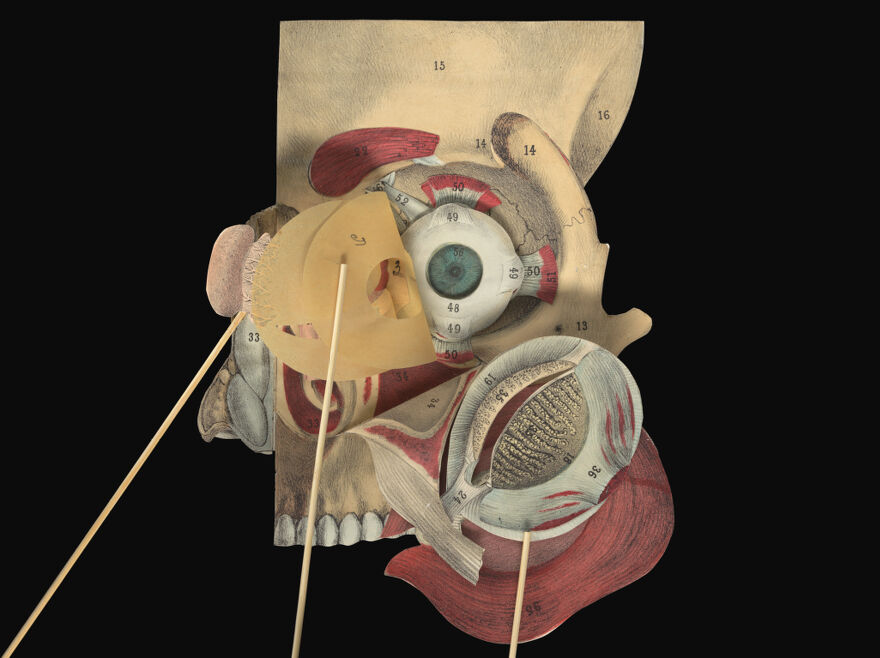

A pictorial manikin, or, Movable atlas / by Professor G.J. Witkowski.

- Witkowski, G.-J. (Gustave Joseph), 1844-1923. Anatomie iconoclastique. English

Credit: A pictorial manikin, or, Movable atlas / by Professor G.J. Witkowski. Source: Wellcome Collection.